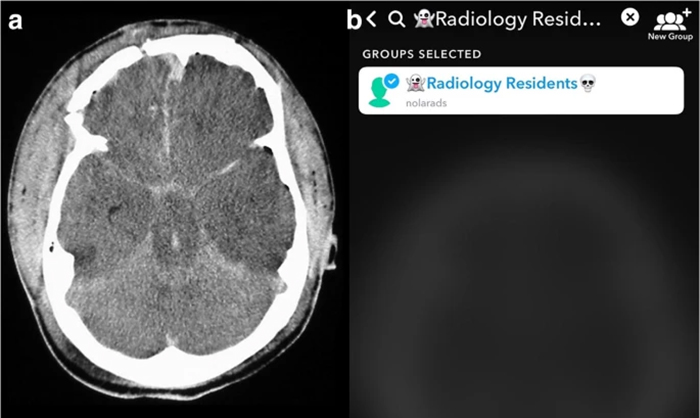

The team compared image analysis and interpretation by radiology residents using Snapchat on smartphones with conventional analysis on a single screen in the resident conference room.

“All cases used were diagnoses considered to require emergent, non-routine communication on the order of minutes to the ordering health care provider,” notes Bradley Spieler, MD, Vice Chairman of Research in the Department of Radiology at LSU Health New Orleans School of Medicine. “As such, these types of diagnoses demand prompt imaging recognition as they are considered critical findings which could result in death or significant illness if not acted upon expeditiously.”The team chose Snapchat, a social media app allowing communication via video and digital images with text messaging functionality, not only because of its popularity with young adults, but most importantly because unlike other image based social media platforms, Snapchat allows for the timing of image visibility by users. The ability to specify the length of time an image is visible to a user (or trainee in this scenario) in rendering an image-based diagnosis creates an intriguing potential for innovation in radiologic curricula, particularly as it relates to assigning a metric to diagnostic performance.

“All residents performed better on Snapchat each week,” says Dr. Spieler, who is also an Associate Professor of Radiology, Internal Medicine, Urology, & Cell Biology and Anatomy at LSU Health New Orleans. “Their accuracy rate was higher using Snapchat than a traditional classroom screen.”

Spieler says, “We believe that the results from this pilot study could facilitate a promising and novel training method in enhancing recognition of imaging diagnoses, particularly those of life-threatening nature, which could be applied to the evolving landscape of distance learning.”

Other LSU Health New Orleans authors include Drs. Dane Mackey, Caitlin Henry, Raman Danrad, Carl Sabottke, Claude Pirtle, and Eric Wallace in Diagnostic Radiology; and Dr. Jason Mussell in Cell Biology and Anatomy. Dr. Catherine Batte in the Department of Physics & Astronomy at Louisiana State University also contributed.The authors conclude, “Our hope is that this investigation can aid in the promotion of active learning and lecture participation as well as to explore metrics for gauging diagnostic performance and pattern recognition in image-based curricula both within the classroom and in remote teaching formats. A larger sample size and more intricate study designs, for example, with the adjunct of eye tracking, may support the burgeoning role that handheld devices and imaged-based social media applications like Snapchat can play in learning at all levels of education especially in the context emergency radiology.”